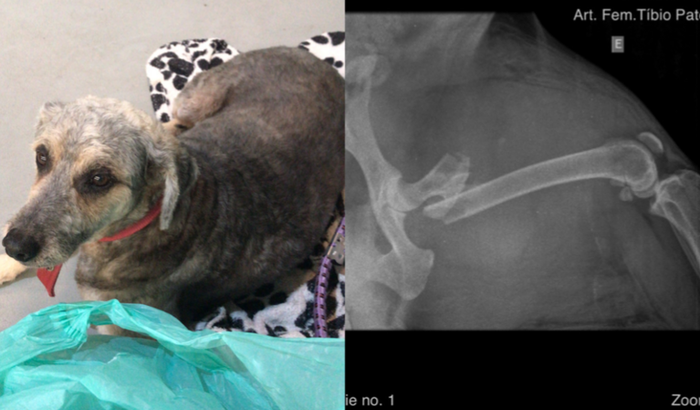

Opa gente, eu sou o Carlos, o dono da Maria Xuxu Liane. Ela foi atropelada e fraturou sua pata traseira. Agora ela precisa de ajuda para podermos fazer a cirurgia o mais rápido possível! Assim preciso do suporte de vocês com uma doação simbólica, onde todo o valor será usado nos seus exames pré e pós operatório, tão quanto seus remédios e tratamento. Peço muito o apoio de vocês família.